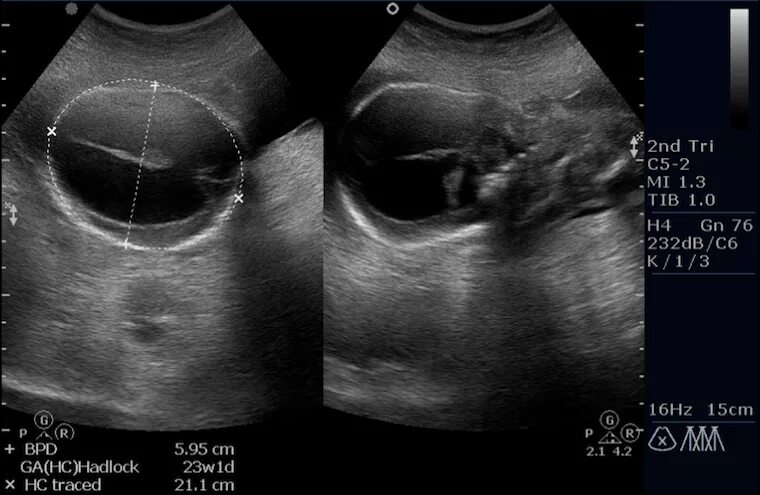

Узи аномалий